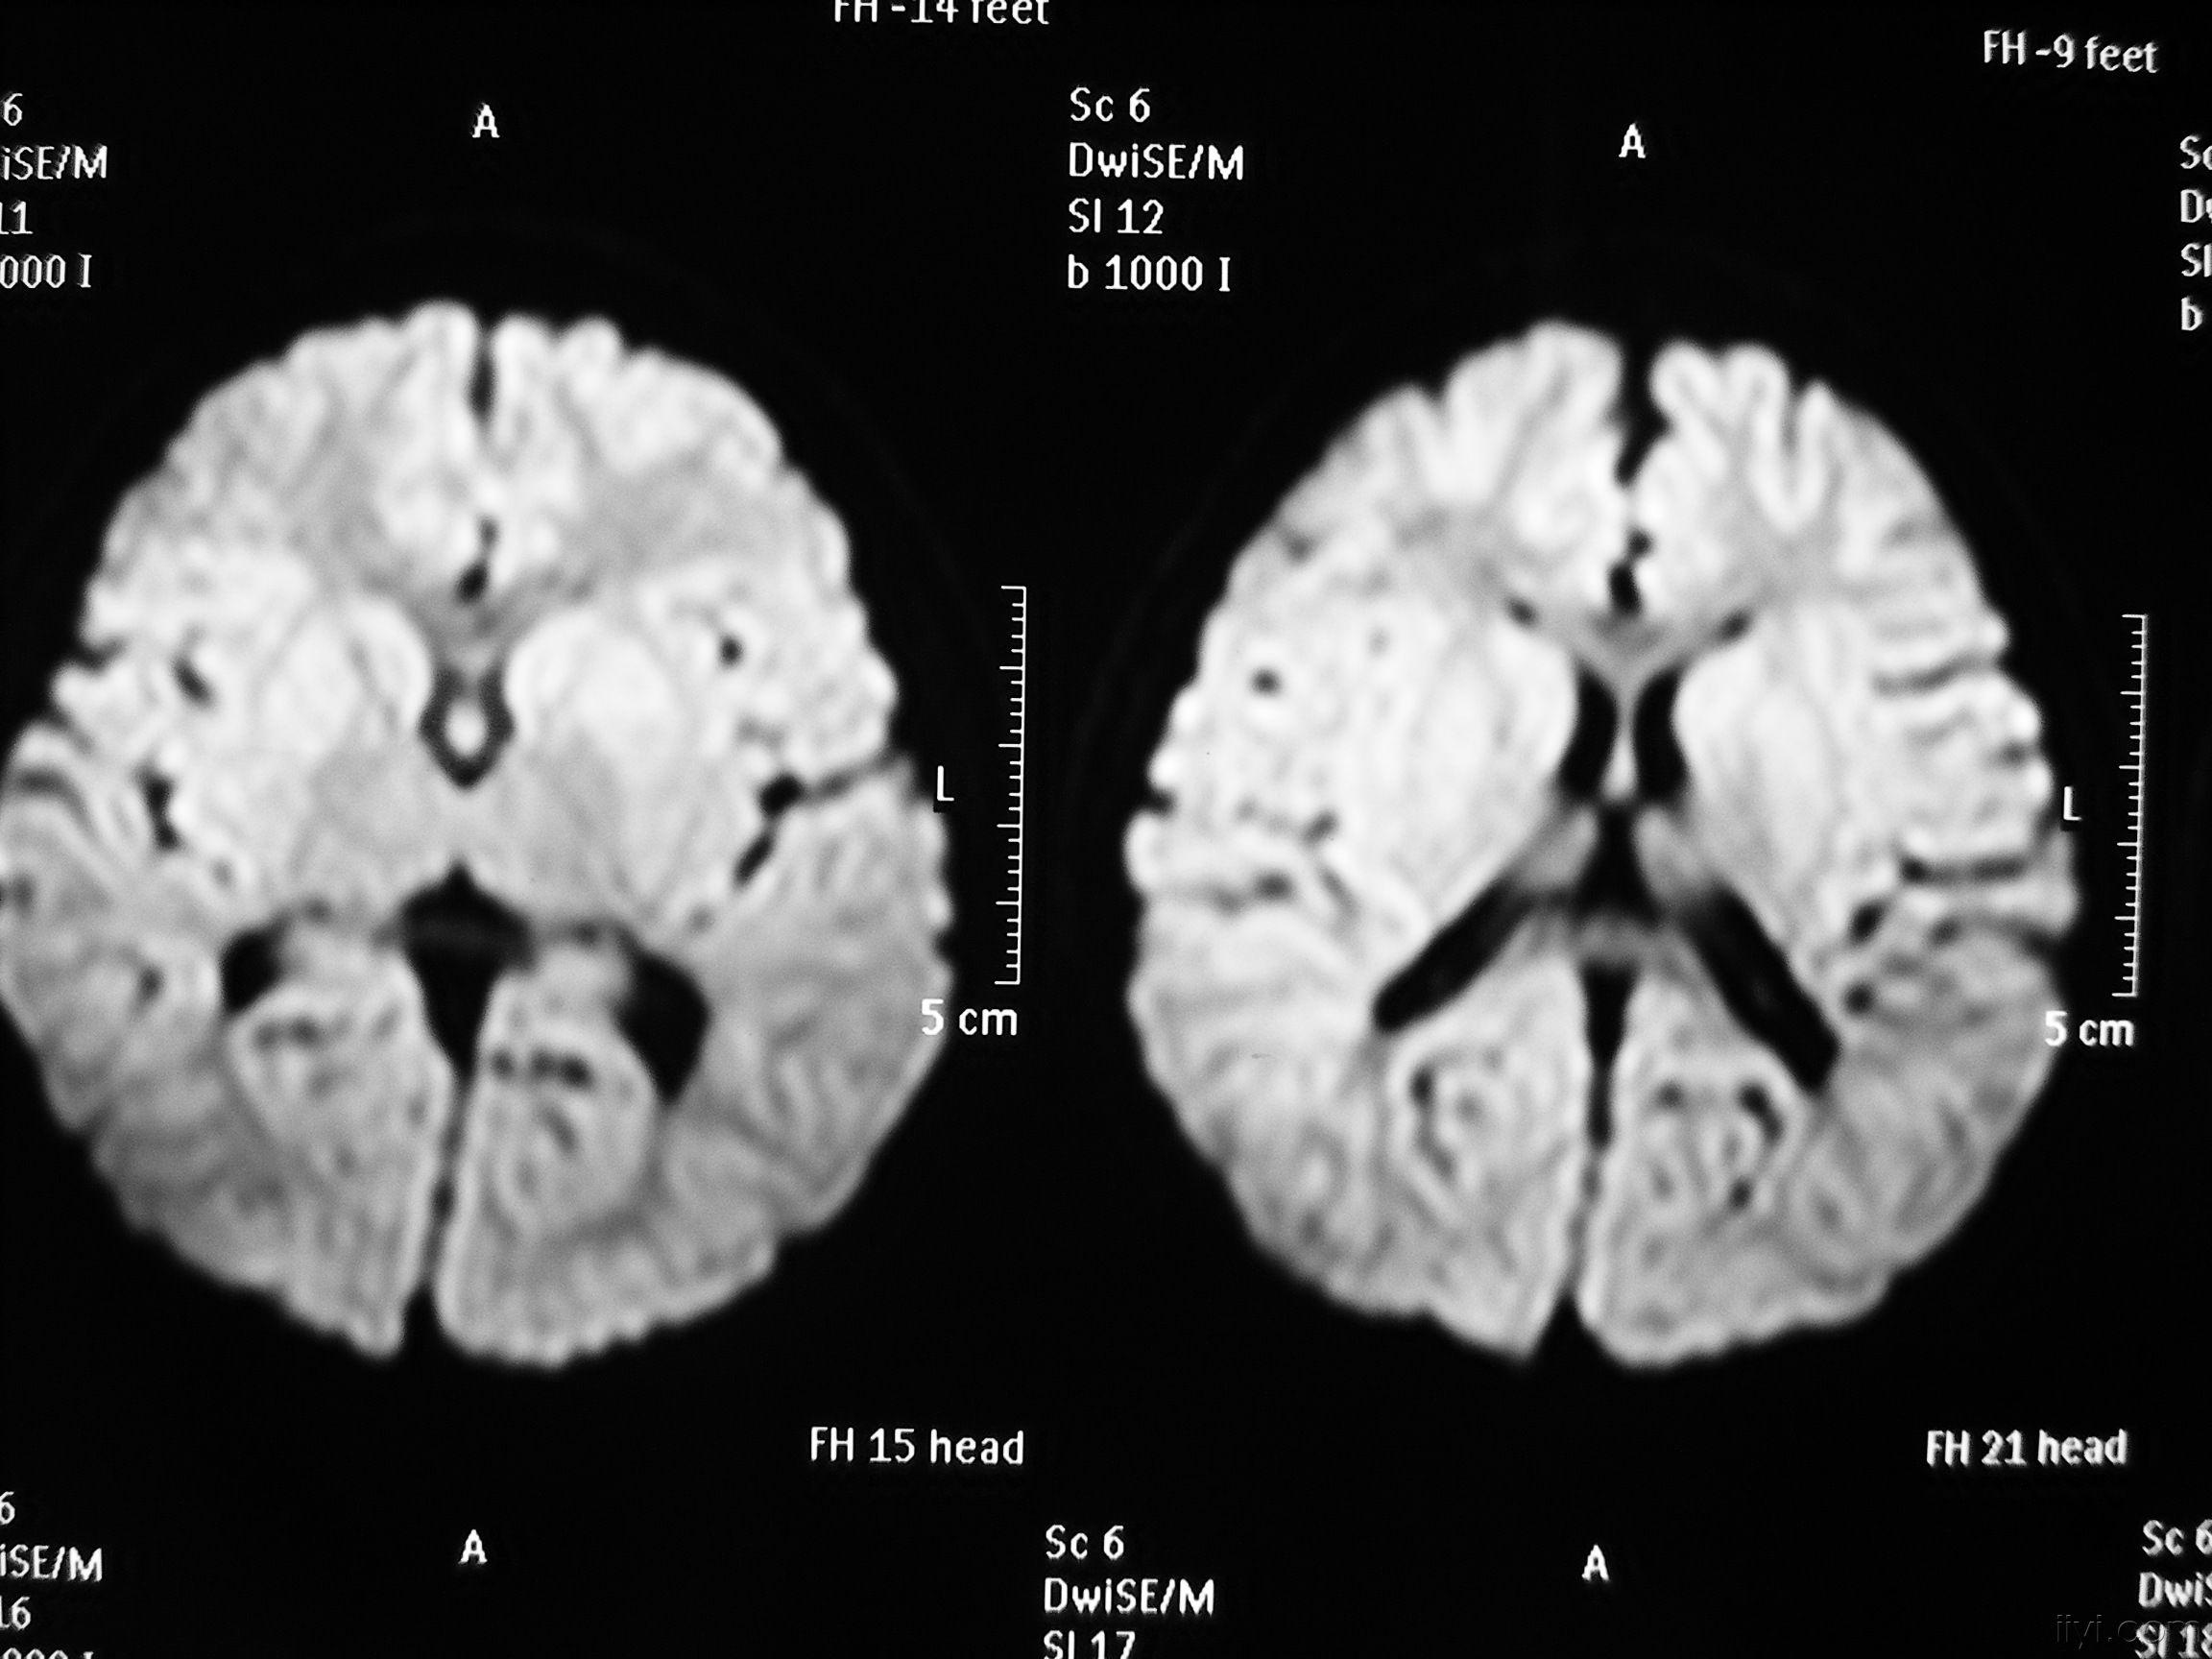

影像学发生于侧脑室周围,侧脑室扩大,脑白质减少。扩大的侧脑室外缘常不规则为其特点,多为双侧脑室同时扩大。脑白质减少,脑皮层与脑室侧缘相近。MRI T1呈低信号,T2呈高信号。